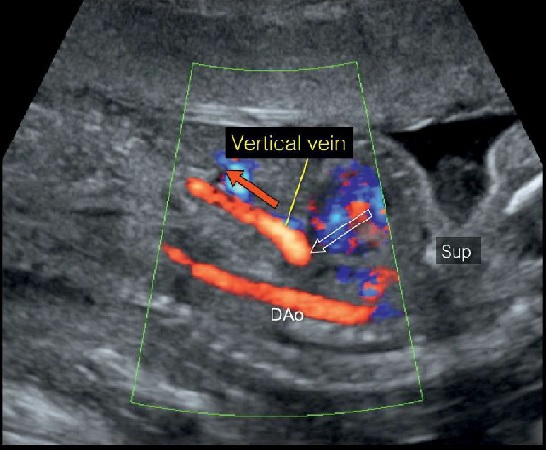

- Tĩnh mạch hợp lưu (confluent vein) đổ vào tĩnh mạch dọc xuống (descending vertical vein), có chiều hướng dòng chảy xuống dưới, gặp thể dưới tim (infracardiac), chiều của tĩnh mạch dọc (vertical vein) lúc này cùng chiều với động mạch chủ xuống (DAO).

Hình 15: Thai nhi TAPVR thể dưới tim. Mặt cắt chẩn đoán tối ưu là mặt cắt dọc ngực bụng, dùng Doppler màu, ta thấy động mạch chủ xuống (DAo) nằm phía sau, song song phía trước động mạch chủ bụng là một mạch máu (mũi tên đỏ) có nguồn gốc từ ngực chạy vào gan. Mạch máu này chính là tĩnh mạch dọc xuống (vertical descending vein), cùng chiều dòng chảy với động mạch chủ xuống do vậy có cùng màu trên hình ảnh Doppler màu. Vị trí xuất phát của tĩnh mạch dọc xuống (vertical descending vein) là ở phía sau tim (mũi tên rỗng).